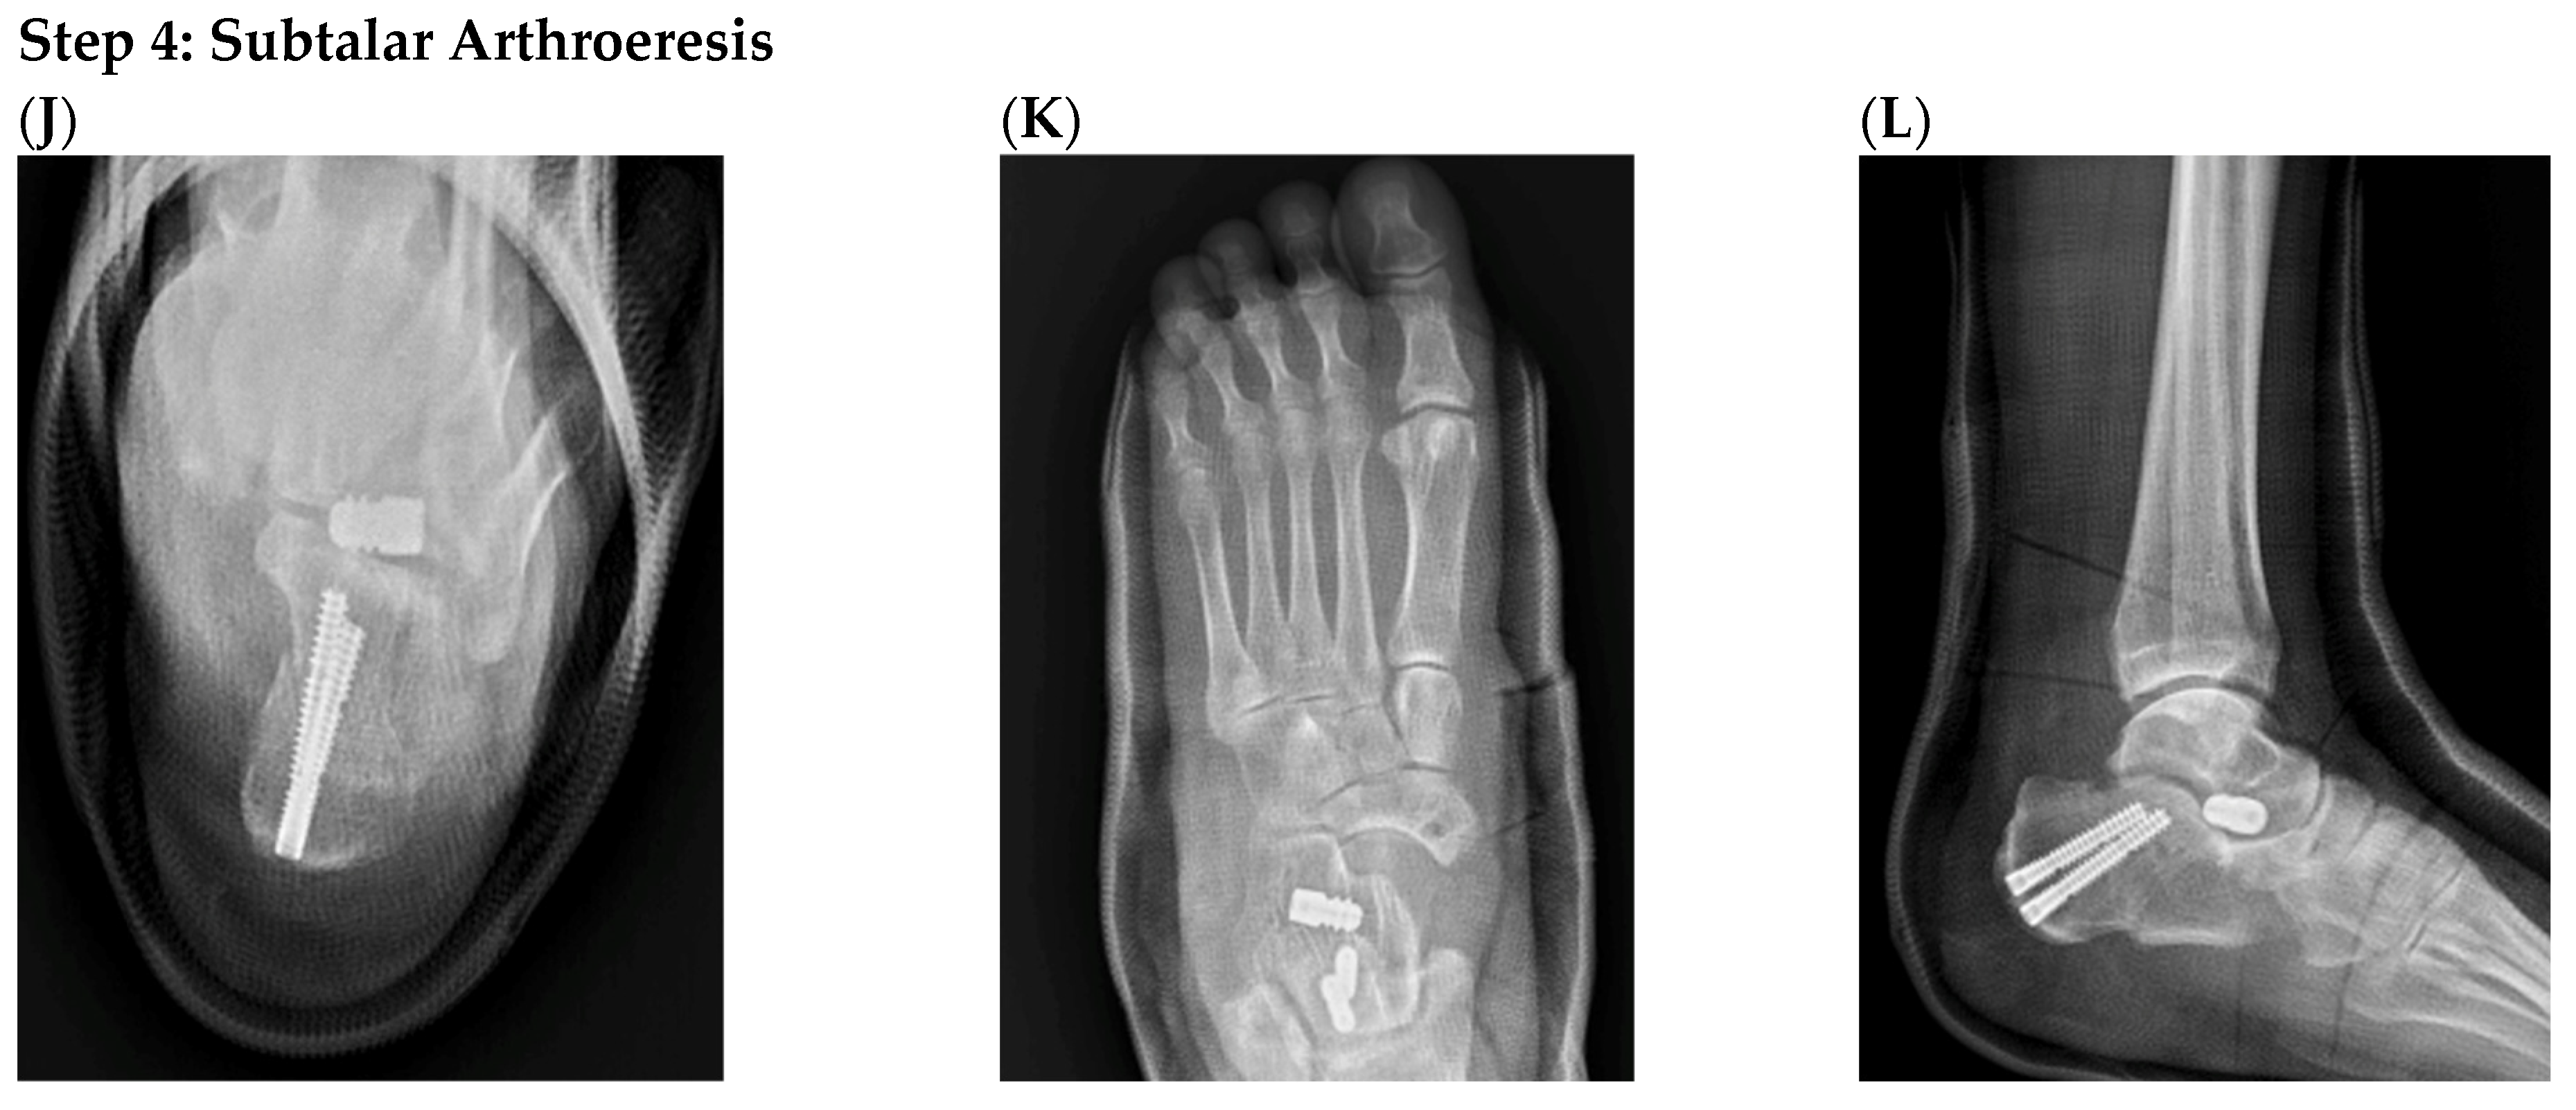

3.6. Representative Case

| Parameter | Preoperative | Postoperative | 24 Months of Follow-Up | p-Value |

|---|---|---|---|---|

| Meary angle (AP, °) | 24.2 ± 7.4 | 9.2 ± 4.1 | 8.6 ± 4.1 | <0.001 |

| Meary angle (Lateral, °) | 9.96 ± 2.3 | 1.92 ± 1.4 | 2.05 ± 1.6 | <0.012 |

| Calcaneal pitch (°) | 10.64 ± 4.87 | 15.78 ± 3.33 | 15.55 ± 4.25 | <0.01 |

| Talonavicular coverage angle (°) | 14.53 ± 6.67 | 3.46 ± 1.56 | 3.58 ± 0.78 | <0.024 |